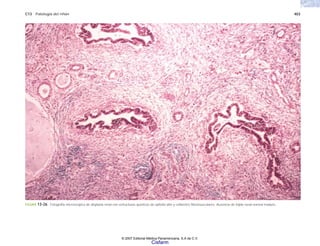

FIGURA 6-11. Pseudomonas aeruginosa. a) Mucosa intestinal con úlceras bien cir-

necrosante con destrucción de la pared y numerosos bacilos gramnegativos (rojos).

Tinción de Gram 40x.

(b)

(a)